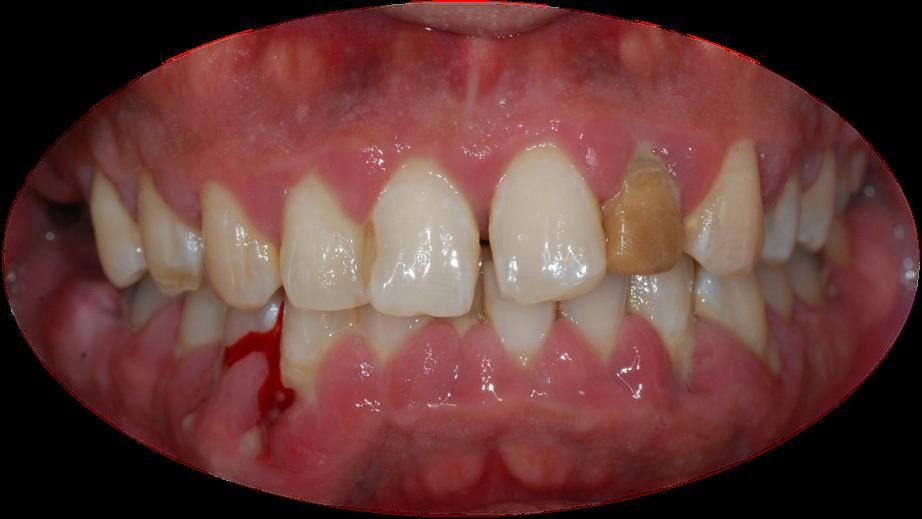

양치할 때, 침을 뱉을 때 피가 비치면 잇몸병을 의심할 수 있다. 이 밖에도 △잇몸에서 피가 난다 △잇몸이 빨갛게 변하거나 붓는다 △잇몸이 주기적으로 들뜨고 근질거린다 △이와 이 사이가 벌어지고 음식물이 많이 낀다 △잇몸이 내려가 점점 치아가 길어 보인다 △나쁜 입 냄새가 난다 △흔들리는 치아가 있다 등 증상이 있다면 잇몸병이 있는지 확인해야 한다.

염증으로 인해 잇몸 결합조직의 부착이 느슨해지면, 치은열구 틈새로 더 많은 치태가 쌓이고, 그로 인해 주변 조직의 파괴 속도가 빨라진다. 또, 더 깊고 넓은 치주낭이 만들어지면 세균성 치태가 더 많이 쌓이는 악순환으로 이어진다. 그래서 잇몸치료의 기본은 '세균성 치태를 물리적으로 제거'하는 데 초점을 둔다.